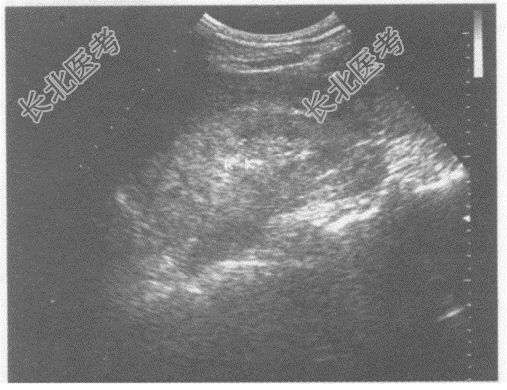

- 单项选择题临床资料:女, 55岁,自述腰痛1年余, 近日尿量减少。

临床物理检查:肾区叩痛。

化验检查: 尿肌酐增高,尿蛋白4+。

超声综合描述: 双肾表面不平,大小正常, 皮质回声增强,皮髓界限不清, 集合系统结构紊乱。

超声提示: A、双肾皮质回声增强

B、双肾萎缩

C、双肾正常声像图

D、双肾弥漫性病变

E、双肾皮质无回声